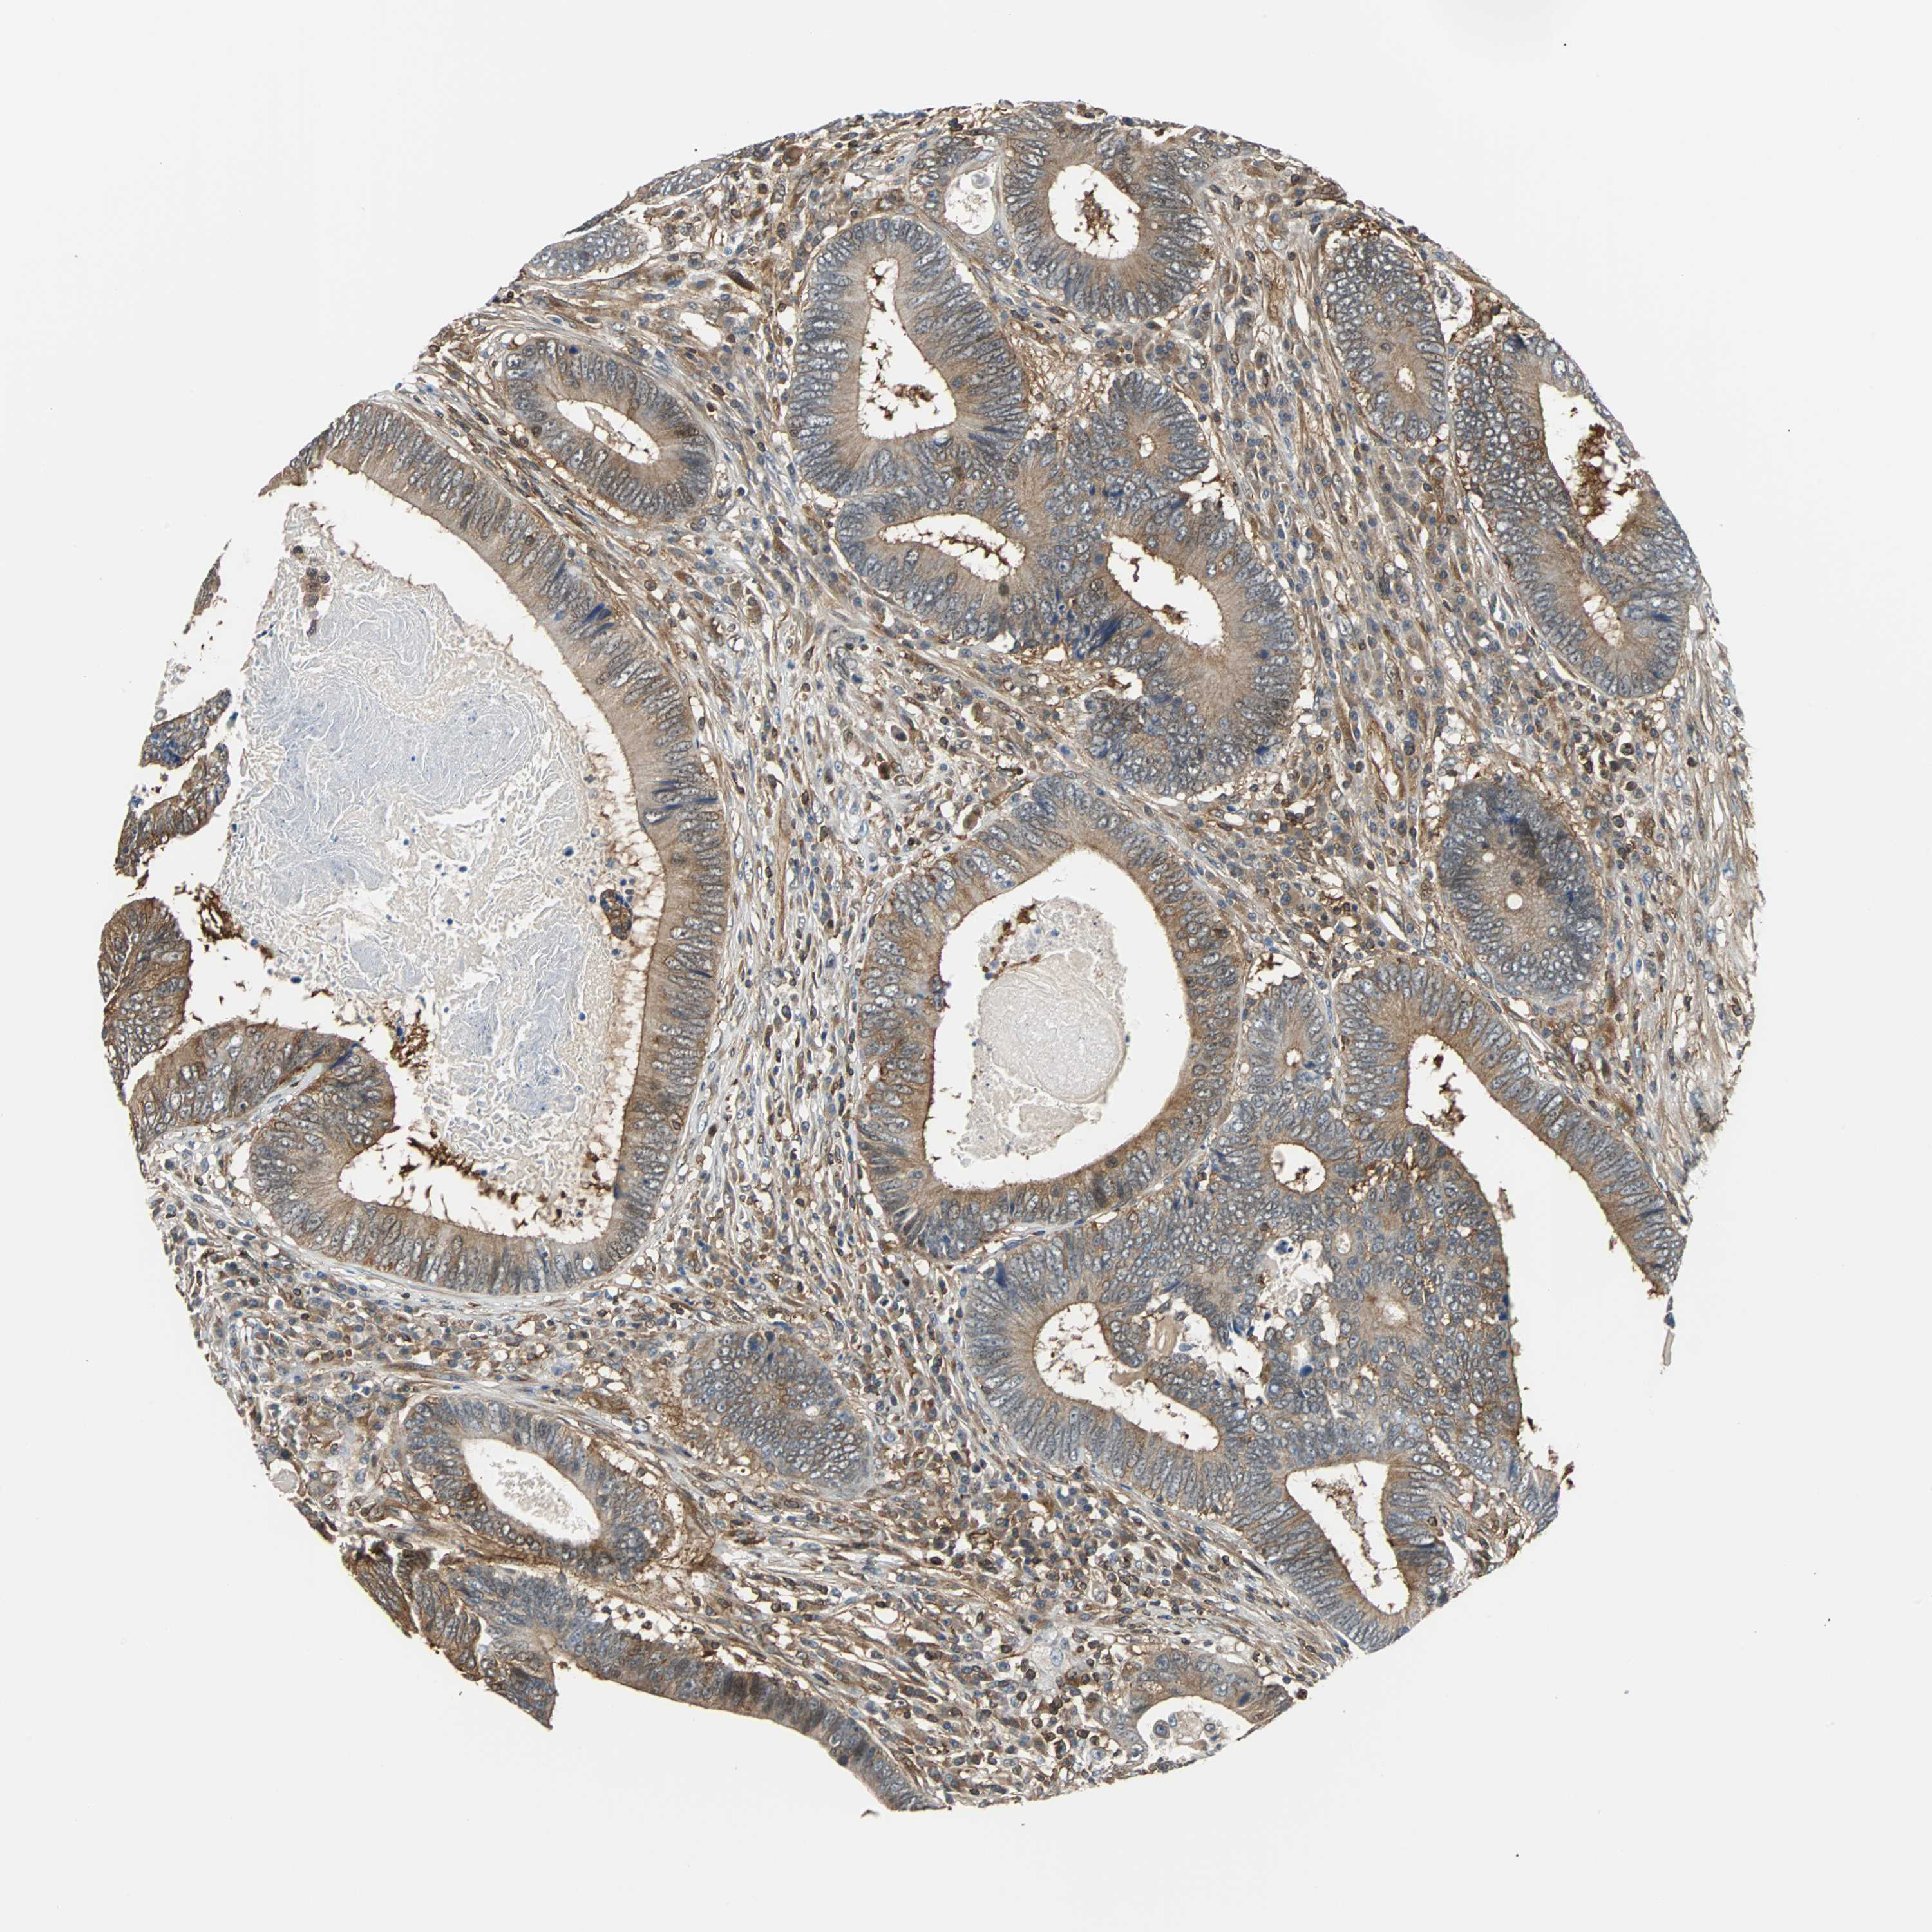

CANCER COLORECTAL CANCER Show tissue menu

Colorectal cancer

Human cancer

Rectum adenocarcinoma